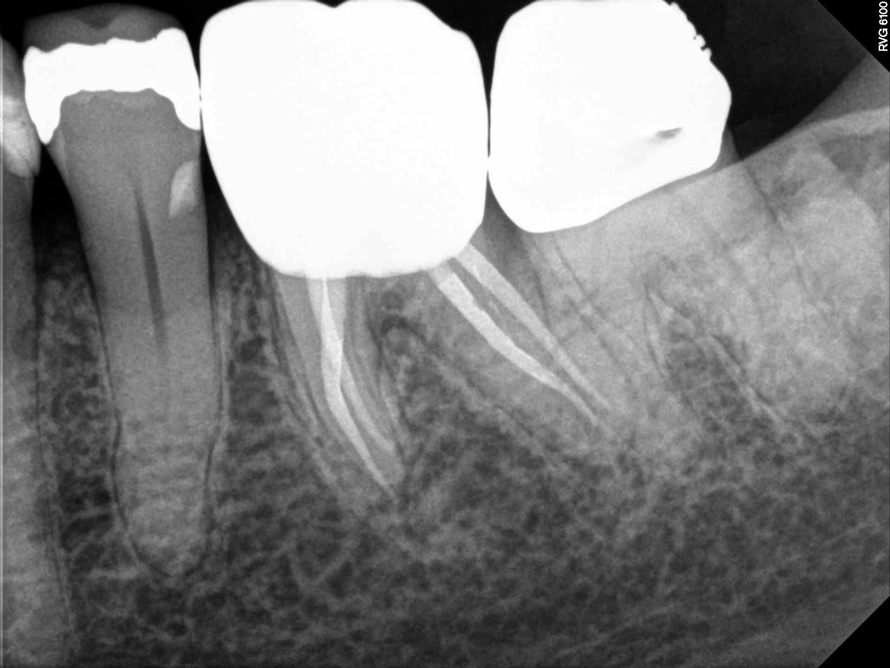

Fig 2. Tooth No. 14 was treated with silver points. In Figure 2, tooth No. 18 with mesial canals treated with Sargenti paste. The hallmark radiographic appearance of this technique is the light radiopacity within the canal system, as in Figure 3.

Figure 2